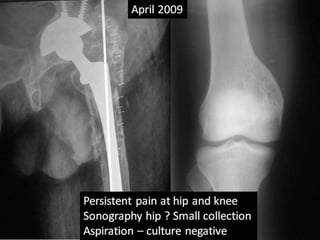

Case summary •Persistent pain in hip and knee since revision. • Hip ultra-sonography in April 2009 – small pocket – aspiration negative. • No relief with antibiotics. • Removal of Solution hip in Sept 2009.

Case summary •Vancouver B3 type peri-prosthetic fracture • Revision THR for shattered femur by Mennen plate with non cemented Solution hip and bone grafting in acetabular wall defects. • Sciatic palsy • Removal of Mennen plate and wires in April 2009 after fracture union.